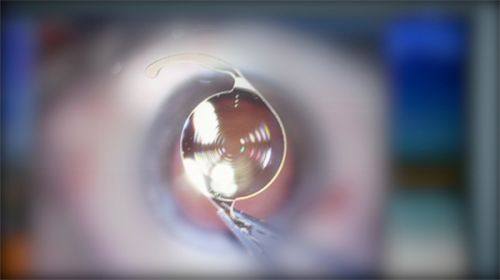

(二)白内障超声乳化摘除联合人工晶体植入术成效佳

1. 医院开展的白内障超声乳化摘除联合人工晶体植入术,能快速、有效地治疗白内障。超声乳化技术能将混浊的晶状体乳化吸出,切口小,修复快。

2. 提供多种类型的人工晶体供患者选择,医生会根据患者的眼部情况和用眼需求,为患者推荐合适的人工晶体,提高患者术后的视觉质量。